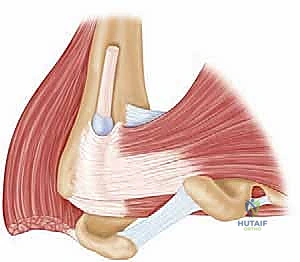

لماذا العضلة الصدرية الكبرى (Pectoralis Major) كبديل؟

العضلة الصدرية الكبرى هي عضلة صدرية ضخمة وقوية للغاية، مسؤولة عن تقريب الذراع وتدويرها للداخل. نظراً لقربها التشريحي من مفصل الكتف، واتجاه أليافها العضلية الذي يشبه إلى حد كبير اتجاه ألياف عضلة تحت الكتف، تُعد "المتبرع" المثالي. في هذه الجراحة، يقوم الأستاذ الدكتور محمد هطيف بفصل جزء من وتر العضلة الصدرية الكبرى ونقله وتثبيته في مكان ارتكاز عضلة تحت الكتف التالفة (Lesser Tuberosity).

الخطوة الثالثة: حصاد وتر العضلة الصدرية الكبرى

هذه هي الخطوة الأكثر دقة. يقوم البروفيسور هطيف بتحديد الجزء العلوي (الترقوي) أو الجزء السفلي (القصي) من العضلة الصدرية الكبرى، بناءً على التقنية الأنسب للمريض. يتم فصل الوتر بعناية فائقة من مكان ارتكازه على عظمة العضد، مع الحفاظ التام على العصب المغذي (Pectoral Nerves) والأوعية الدموية لضمان بقاء العضلة حية وقادرة على الانقباض.

الخطوة الخامسة: نقل وتثبيت الوتر

يتم تمرير وتر العضلة الصدرية الكبرى تحت العضلة ذات الرأسين (Biceps) أو فوقها (حسب الحالة)، وسحبه نحو المنطقة العظمية المحضرة. يستخدم الدكتور هطيف أحدث الخطاطيف الجراحية (Suture Anchors) المصنوعة من التيتانيوم أو المواد القابلة للامتصاص لتثبيت الوتر بقوة هائلة في العظم.

يتم التأكد من الشد المناسب (Tensioning)؛ فإذا كان الوتر مشدوداً جداً قد يتمزق، وإذا كان مرتخياً لن يؤدي وظيفته. هذه الخطوة تتطلب "حسّاً جراحياً" لا يتوفر إلا لجراح متمرس مثل الأستاذ الدكتور محمد هطيف.